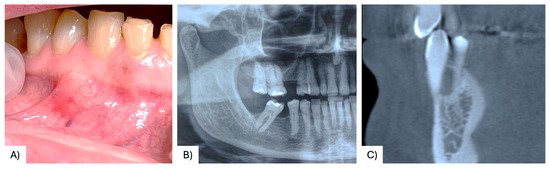

| 37 | Present case | 68 F | Maxilla, between #4.3, #4.4 | Asymptomatic nodule | 15 mm | Radiolucency with a defined margin area | Alveolar bone resorption | Excisional biopsy, curettage | No recurrence at 6 months follow-up | 2025 |